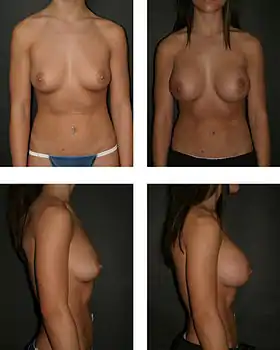

The pre-operative aspects (left), and the post-operative aspects (right) of a bilateral, sub-muscular emplacement of 350 cc saline implants through an infra-mammary fold (IMF) incision | |

The surgical implantation approach creates a spherical augmentation of the breast hemisphere, using a breast implant filled with either saline solution or silicone gel; the fat-graft transfer approach augments the size and corrects contour defects of the breast hemisphere with grafts of the adipocyte fat tissue, drawn from the person's body.

The operating room time of post–mastectomy breast reconstruction, and of breast augmentation surgery is determined by the emplacement procedure employed, the type of incisional technique, the breast implant (type and materials), and the pectoral locale of the implant pocket.[47]

- Submuscular – The breast implant is emplaced beneath the pectoralis major muscle, without releasing the inferior origin of the muscle proper. Total muscular coverage of the implant can be achieved by releasing the lateral muscles of the chest wall – either the serratus muscle or the pectoralis minor muscle, or both – and suturing it, or them, to the pectoralis major muscle. In breast reconstruction surgery, the submuscular implantation approach effects maximal coverage of the breast implants.